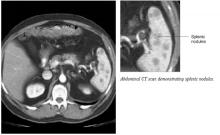

A 33-year-old African American woman came to the office with a 2-week history of skin lesions and itching. The lesions started with a single blister on her left elbow; numerous other blisters subsequently appeared on her forearm and hands. One week before this visit, she had been given a presumptive diagnosis of bullous impetigo and was treated with cephalexin.

Despite the antibiotics, other lesions soon appeared in the nuchal and breast folds, axillae, and scalp areas. Several had ruptured, producing purulent, malodorous material. She had no known allergies, no medical problems aside from obesity, and no significant family history or recent travels. She denied any illicit drug use and had not been on any medications.

On physical exam, 1 large bulla was seen on the fourth digit of her left hand (Figure 1). The patient was obese, and inspection of the skin folds of her abdomen showed multiple suppurative lesions and erosions where previous bullae were found (Figure 2). No oral or gingival erosions were seen. Labs showed a white blood cell (WBC) count of 10.5 x109L], hemoglobin of 11.0 g/dL, and hemoglobin A1cof 5.5; liver function tests were normal. Gram stain showed no WBC and had rare Gram-positive bacilli. Potassium hydroxide prep of a skin lesion scraping showed no fungal elements. A herpes culture was performed along with a punch biopsy.

FIGURE 1

Bulla on the index finger

Left index finger bulla, which appeared 10 days after onset of disease.

FIGURE 2

Multiple bullae on the trunk

Right breast and abdominal folds with multiple flaccid bullae and denuded areas.